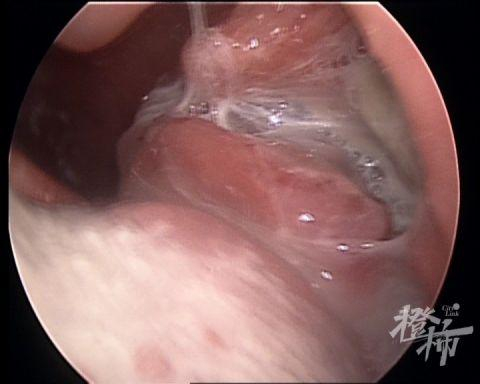

耳鼻喉科主任熊高云主任医师通过检查发现,李先生左侧扁桃体异常肿大,表面有黄白色分泌物,不易去除;右侧扁桃体正常,触摸左侧颌下区淋巴结肿大,活动欠佳,高度怀疑是“扁桃体淋巴瘤”,立即进行喉部增强CT检查。结果显示:左侧扁桃体明显增大,颈动脉区肿大淋巴结,建议手术穿刺活检。

意识到这并不是简单的“扁桃体发炎”,李先生立即接受了扁桃体活检术。熊高云主任在表麻下做了左侧扁桃体活检术,并送病理检查。病理报告结果:首先考虑弥漫大B细胞淋巴瘤。随后,李先生在家人的陪同下转至医院的血液科做进一步治疗。

尤其是单侧扁桃体肿大,且表面粗糙,容易出血,质地硬,甚至出现溃疡、坏死,就需要引起高度重视,考虑是否为扁桃体恶性肿瘤。